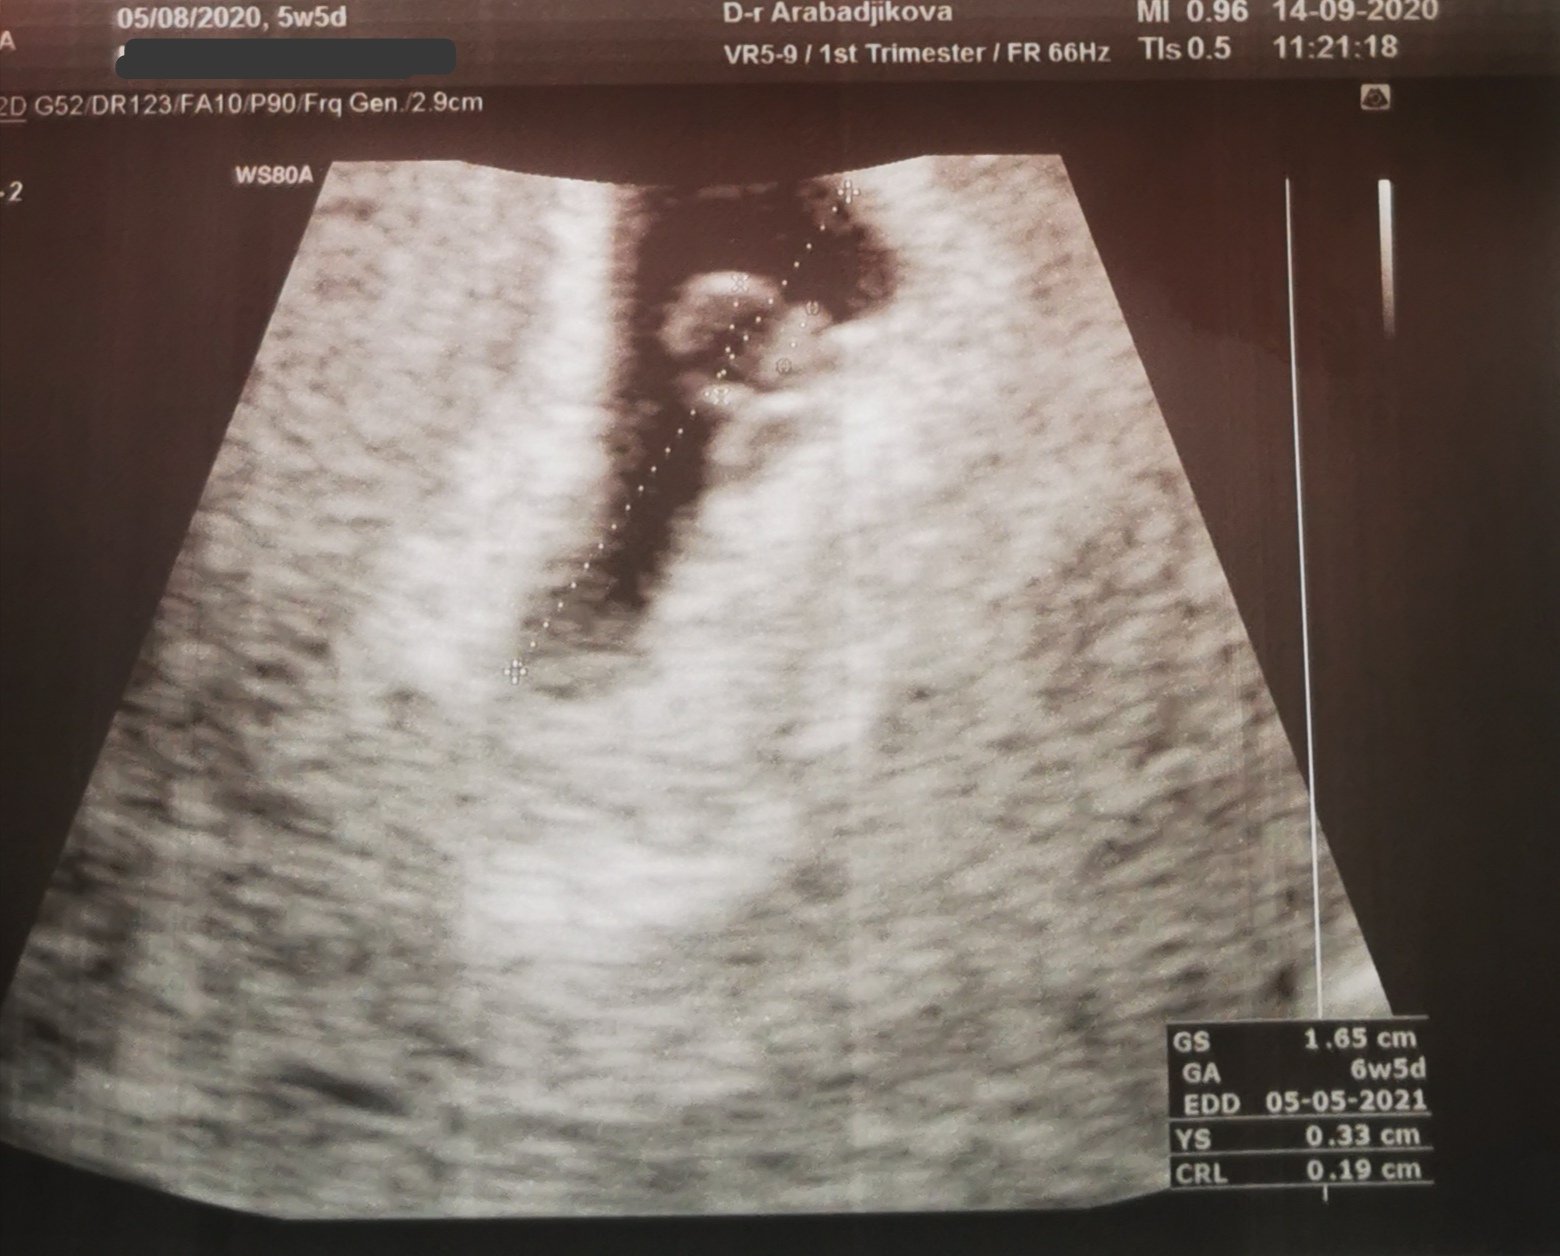

Форумът обсъжда бременност, положителни тестове за бременност, термини на бременността, симптоми и преживявания на бъдещи майки. Освен това се включват медицински въпроси като тромбофилия и терапия с фраксипарин, както и дискусии за деца, включително теми за детски градини и здравословно развитие на децата.

Във форума се споделят преживявания и притеснения, свързани с бременността. Бъдещите майки обсъждат своите емоции, като вълнение от положителни тестове и преживявания по време на прегледи и лечение. Те също така изразяват своите опасения относно потенциални проблеми, като хипертония или тромбофилия, както и справянето със загубата на бременност.